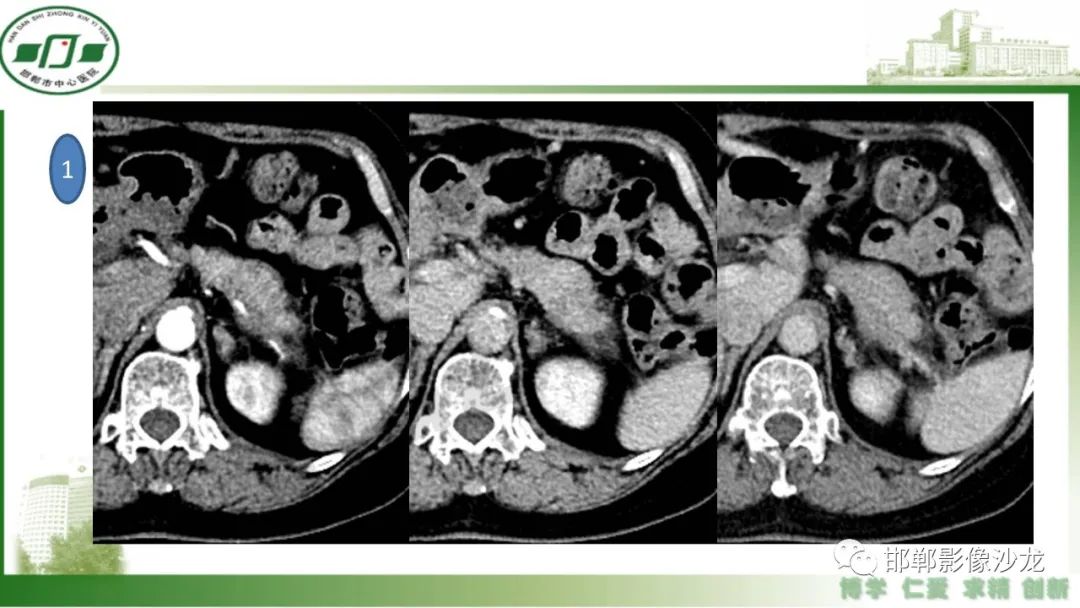

肿块性胰腺炎与胰腺癌的临床、实验室检查、影像学表现有时候很难鉴别,但两者的临床处理、预后又有很大的不同,因此我们平时工作中需要注意两者之间的区别,谨慎诊断,力争为患者及临床带来更大的帮助。